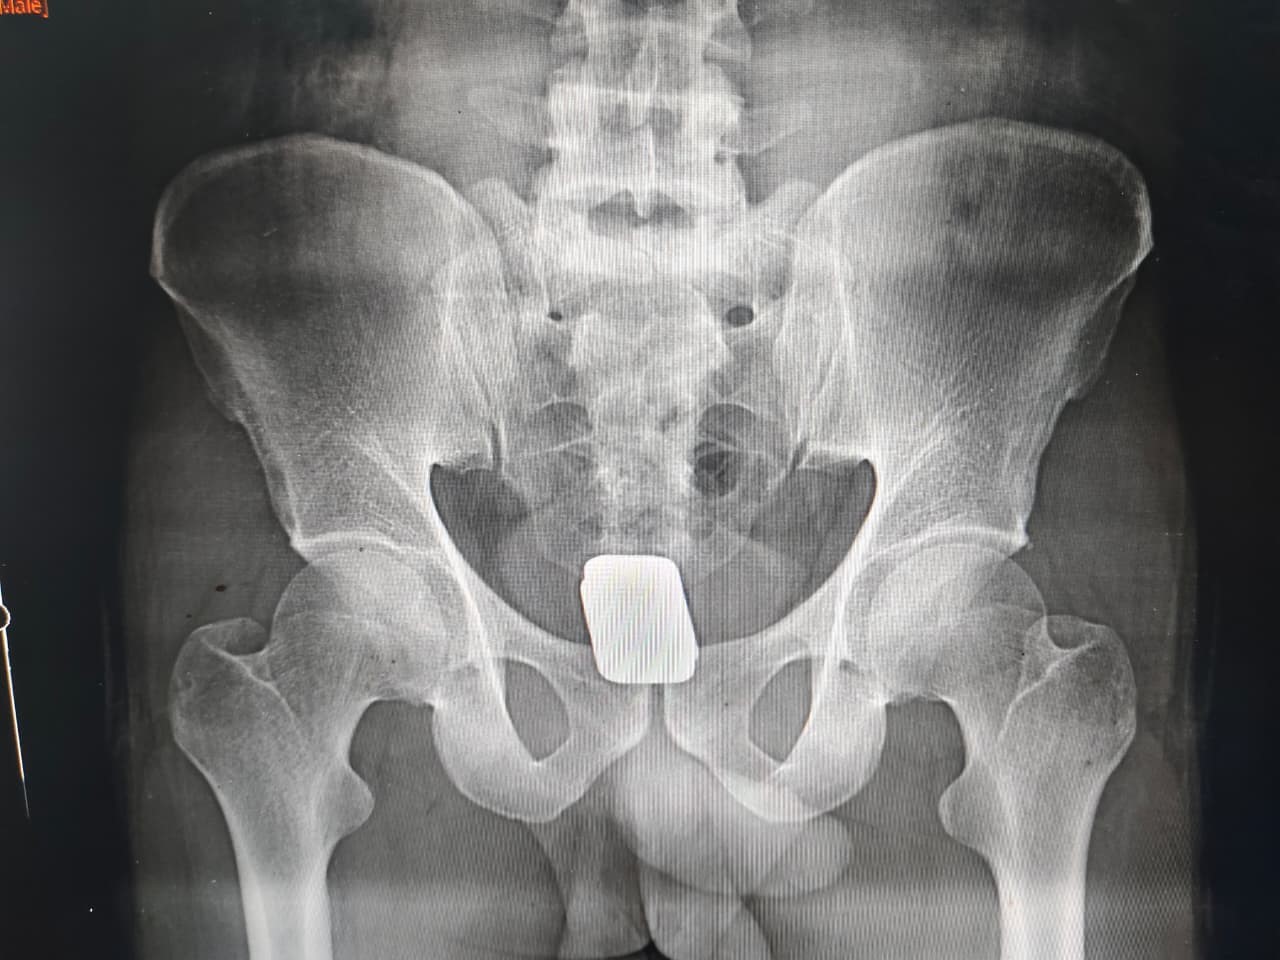

চাঁপাইনবাবগঞ্জের সোনামসজিদ আন্তর্জাতিক চেকপোস্ট (আইসিপি) থেকে ২৩১.৮১ গ্রাম স্বর্ণসহ এক ব্যক্তিকে আটক করেছে মহানন্দা ব্যাটালিয়ন (৫৯ বিজিবি)। বিজিবি সূত্রে জানা গেছে, গত ১২ মার্চ বিকেল আনুমানিক ৫টার দিকে মহানন্দা ব্যাটালিয়ন (৫৯ বিজিবি) এর অধীনস্থ সোনামসজিদ আইসিপিতে কর্মরত বিজিবি সদস্যরা নিয়মিত চেকিং কার্যক্রম পরিচালনা করেন। এ সময় বাংলাদেশি নাগরিক ময়মনসিংহ জেলার গফরগাঁও থানার জয়ধরখালির বড় বড়াই কাউরাইদ এলাকার মো. রফিকুল ইসলামের ছেলে মো. সানি মাই (২৭) (পাসপোর্ট নং- A12776759) কে সন্দেহভাজন হিসেবে আটক করা হয়। চেকিংয়ের সময় বিজিবির আর্চওয়ে মেটাল ডিটেক্টরে তার শরীরে ধাতব বস্তুর উপস্থিতি ধরা পড়ে। পরে তাকে প্রাথমিক জিজ্ঞাসাবাদ করলে তিনি স্বর্ণ থাকার কথা স্বীকার করেন। পরবর্তীতে তাকে শিবগঞ্জ উপজেলা স্বাস্থ্য কমপ্লেক্সে নিয়ে যাওয়া হয় এবং থানা পুলিশের উপস্থিতিতে এক্স-রে করা হলে তার পায়ুপথ থেকে ২টি স্বর্ণের বার উদ্ধার করা হয়।

উদ্ধারকৃত স্বর্ণের বার দুটি চাঁপাইনবাবগঞ্জ স্বর্ণ জুয়েলারি সমিতি কর্তৃক পরীক্ষা করে খাঁটি স্বর্ণ বলে নিশ্চিত করা হয়েছে। যার মোট ওজন ২৩১.৮১ গ্রাম এবং বর্তমান বাজার মূল্য প্রায় ৫৩ লাখ ৯৪ হাজার ৬০০ টাকা।